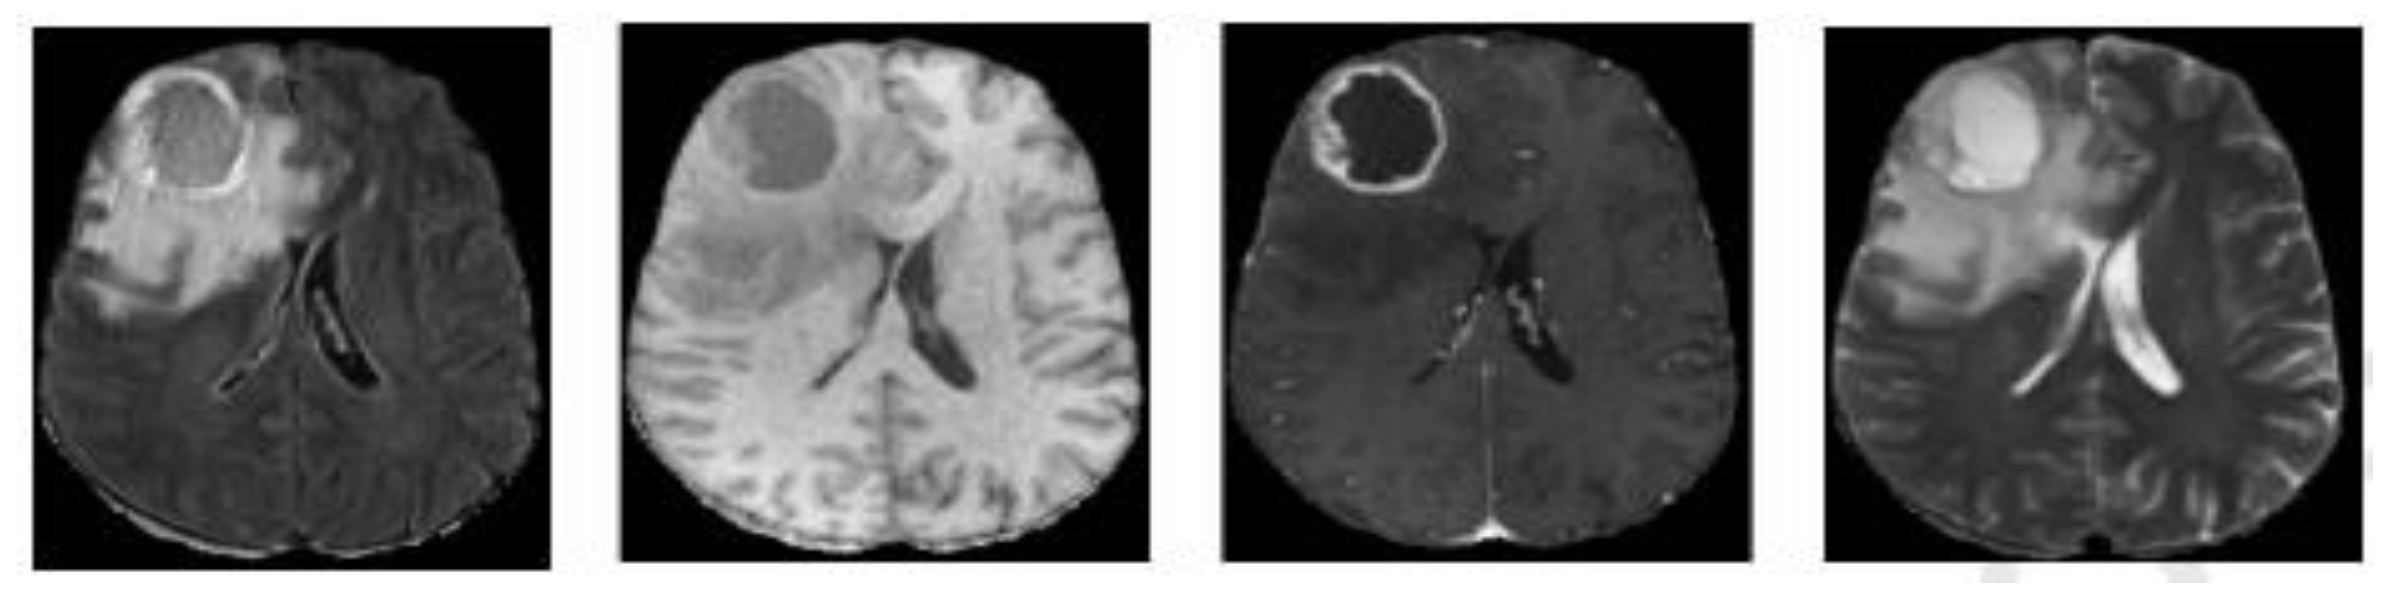

2.1. Data and Data Preparation

2.1.1. Dataset

2.1.2. Data Preparation